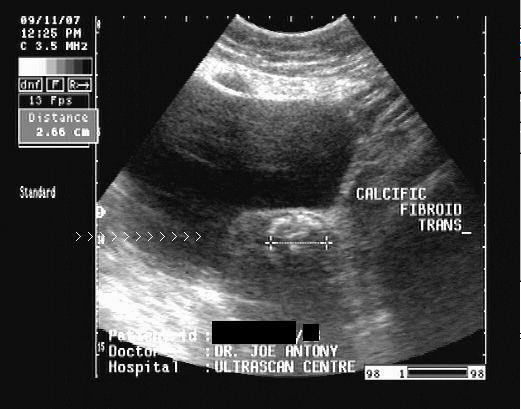

Calcified fibroid

Sonography of fibroid with calcification

This middle aged female patient complained of pain in the suprapubic region. Ultrasound imaging revealed a small uterus with a calcific well-defined, intramural mass in the lower part of the body of uterus. There is clear acoustic shadowing posterior to the calcific lesion. These findings suggest a calcific fibroid of the uterus. Fibroids are often known to undergo calcificaiton in elderly females.